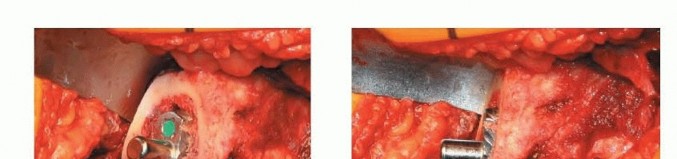

2. تحضير الحُق

قبل التجويف (reaming)، يجب رؤية محيط الحُق بالكامل، والجدار الإنسي، وعلامة الدمعة مباشرة.

الشكل التوضيحي 2: تحضير الحُق. أ. التجويف الأولي لتوسيع الحُق بالكامل. ب. التجويف مكتمل للجدار الإنسي. ج. يستمر التجويف بشكل متسلسل بزاوية تبعيد 35 إلى 45 درجة و10 إلى 20 درجة من التدوير الأمامي.

يجب أن يتم التجويف الأولي بضغط معتدل حتى يتم تقييم جودة العظم. الهدف من التجويف الأولي هو توسيط المجوّف بالكامل. يجب إزالة الحفرة الكوتيلويدية دون اختراق الجدار الإنسي. ثم يستمر التجويف بشكل متسلسل. الهدف هو إعادة إنشاء مركز الدوران عن طريق وضع الجانب السفلي الإنسي للمقبس عند مستوى علامة الدمعة مع ميل المكون بزاوية 35 إلى 45 درجة، مع 10 إلى 20 درجة من التدوير الأمامي وتثبيت مبدئي جيد يتم الحصول عليه عن طريق التثبيت بالضغط.

3. زرع المكون الحقّي

يتم إعادة تقييم وضع الحوض. يتم تصحيح أي إمالة. يتم استخدام المكون التجريبي أو المجوّف لتقييم تغطية العظم للمكون وموضعه. إذا لم يتم تثبيت المكون التجريبي أو المجوّف بشكل صحيح، فقد يكون هناك حاجة إلى المزيد من التجويف. إذا اعتبر ذلك مناسباً، يمكن المضي قدماً في زرع المكون الفعلي.

الشكل التوضيحي 3: زرع المكون الحقّي. أ. يتم استخدام المجوّف النهائي لتقييم وضع المكون، وتغطية العظم، والتثبيت. ب. يتم زرع المكون الحقّي. ج. يستخدم الثقب المركزي للتحقق من أن الكأس مثبت بالكامل. د. يتم إدخال البطانة الفعلية في الكأس.

يجب أن يكون الزرعة الفعلية أكبر بمقدار 1 إلى 2 ملم من المجوّف الأخير. يجب أن يعرف الجراح القطر الفعلي للزرعة، مع الأخذ في الاعتبار أي حافة أو طلاء. الزرعات التي تكون أكبر من حجم المجوّف الأخير بمقدار 4 ملم أو أكثر ترتبط بخطر الكسر. ثم يتم زرع المكون الحقّي، مع الحرص على توسيط الزرعة. يجب أن يكون الجانب السفلي الإنسي للكأس عند مستوى علامة الدمعة بزاوية 35 إلى 45 درجة من التبعيد و10 إلى 20 درجة من التدوير الأمامي. ثم يتم إدخال البطانة التجريبية أو البطانة الفعلية.